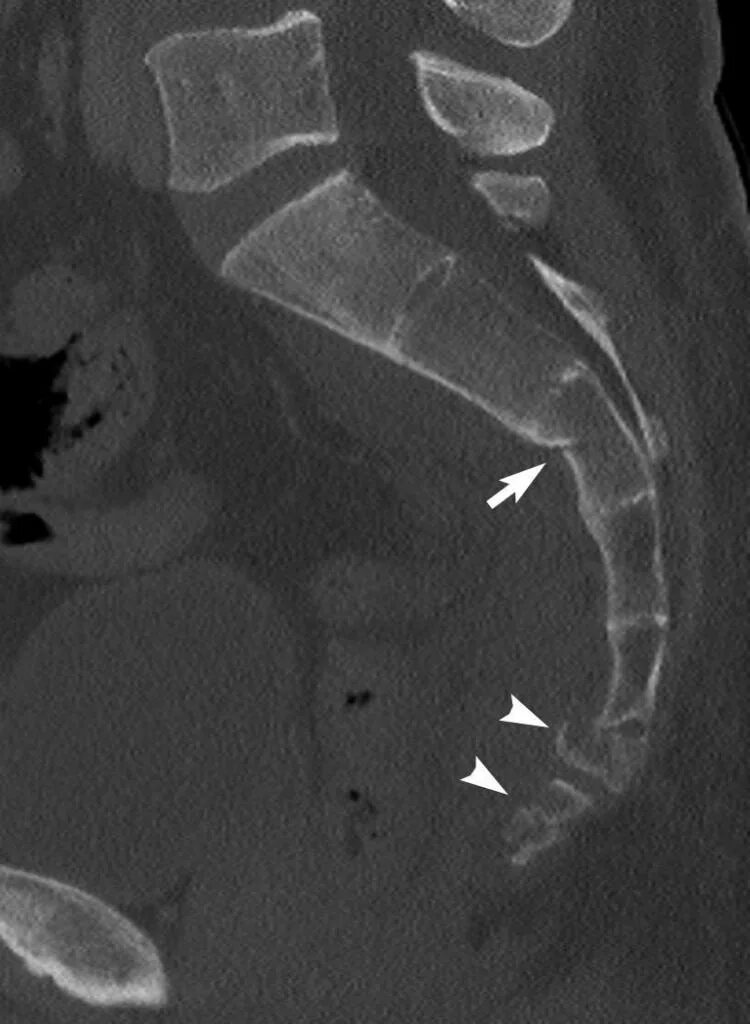

Снимок копчика